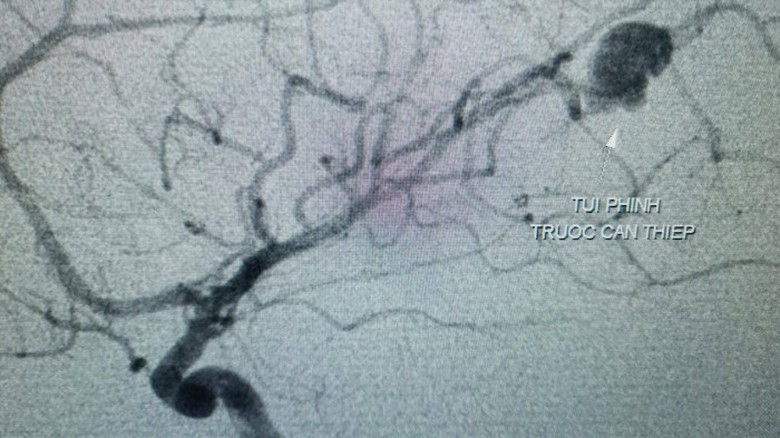

Ngay sau đó, bé được điều trị nội khoa tích cực. Và các bác sĩ đã quyết định chụp mạch máu não bằng kỹ thuật DSA (chụp mạch máu kỹ thuật số xóa nền) để chẩn đoán xác định. Kết quả chụp cho thấy tình trạng xuất huyết não ở bé là do túi phình mạch máu não vỡ.

Hình ảnh túi phình mạch máu não trước can thiệp. Ảnh: Phong Phạm

Ngày 26/7, bệnh nhân được chỉ định nút phình mạch máu não số xóa nền DSA do bác sĩ Trịnh Thành Tính - Khoa Ngoại Thần kinh, BS.CK1 Trần Công Khánh - Phó Khoa Chẩn đoán hình ảnh thực hiện.

Đây là một kỹ thuật hiện đại trong can thiệp túi phình mạch máu não ở trẻ em nói riêng và người lớn nói chung. Các bác sĩ sử dụng 1 ống thông nhỏ, luồn từ động mạch đùi của bé, đưa ống thông lên đến tận các mạch máu não nơi có túi phình, và thả vào túi phình này 1 kết cấu đặc biệt gọi là coil nhằm bít túi phình và nút kín chỗ chảy máu.

Quá trình can thiệp đã diễn ra khá thuận lợi và bít được hoàn toàn túi phình. Thời gian can thiệp 45 phút. Hiện bé đã ổn định, hết nhức đầu, ăn uống lại tốt. TS.BS Hà Tấn Đức, Trưởng Khoa Đột qụy của BVĐKTƯCT cho biết, đây là ca đầu tiên bệnh viện áp dụng kỹ thuật can thiệp này ở trẻ em.